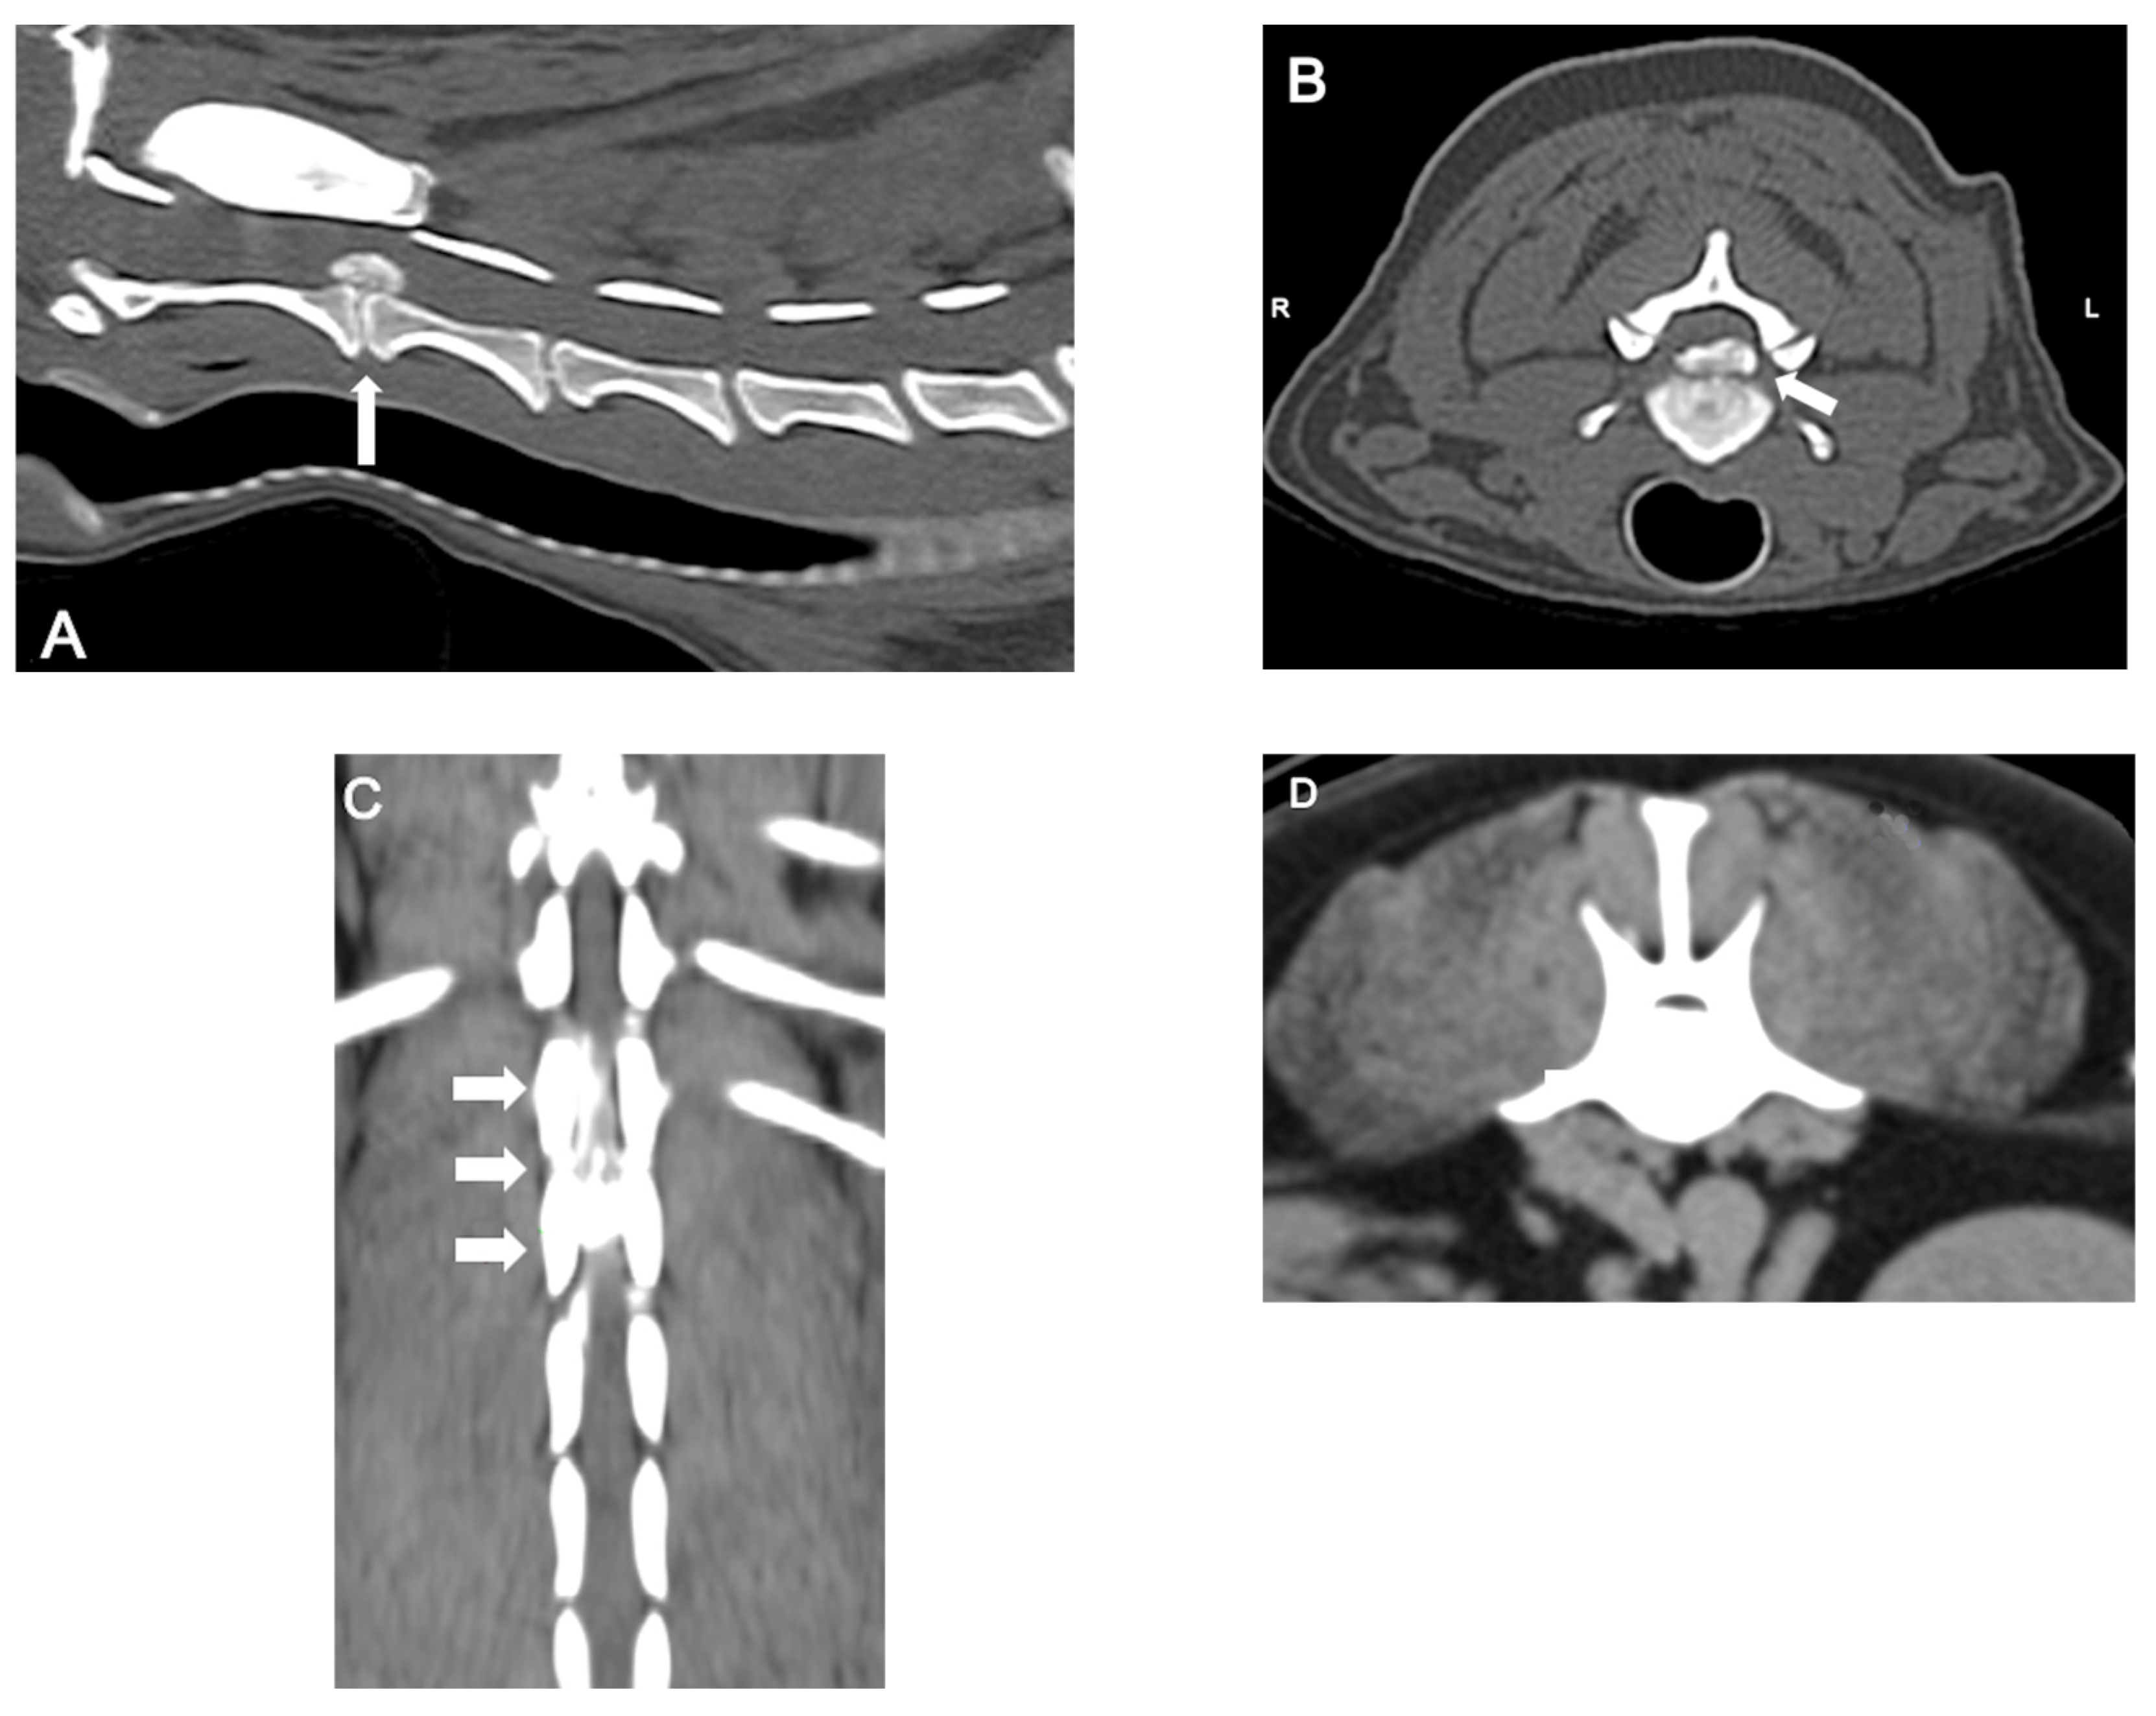

- da Costa, R. C., De Decker, S., Lewis, M. J., Volk, H., & Canine Spinal Cord Injury Consortium (CANSORT-SCI). (2020). Diagnostic Imaging in Intervertebral Disc Disease. Frontiers in Veterinary Science, 7, 588338. [CrossRef]

- Robertson, I., & Thrall, D. E. (2011). Imaging dogs with suspected disc herniation: Pros and cons of myelography, computed tomography, and magnetic resonance. Veterinary Radiology & Ultrasound: The Official Journal of the American College of Veterinary Radiology and the International Veterinary Radiology Association, 52(1 Suppl 1), S81-84. [CrossRef]

- Dennison, S. E., Drees, R., Rylander, H., Yandell, B. S., Milovancev, M., Pettigrew, R., & Schwarz, T. (2010). Evaluation of different computed tomography techniques and myelography for the diagnosis of acute canine myelopathy. Veterinary Radiology & Ultrasound: The Official Journal of the American College of Veterinary Radiology and the International Veterinary Radiology Association, 51(3), 254–258. [CrossRef]

- Noyes, J. A., Thomovsky, S. A., Chen, A. V., Owen, T. J., Fransson, B. A., Carbonneau, K. J., & Matthew, S. M. (2017). Magnetic resonance imaging versus computed tomography to plan hemilaminectomies in chondrodystrophic dogs with intervertebral disc extrusion. Veterinary Surgery: VS, 46(7), 1025–1031. [CrossRef]

- Cooper, J. J., Young, B. D., Griffin, J. F., Fosgate, G. T., & Levine, J. M. (2014). Comparison between noncontrast computed tomography and magnetic resonance imaging for detection and characterization of thoracolumbar myelopathy caused by intervertebral disk herniation in dogs. Veterinary Radiology & Ultrasound: The Official Journal of the American College of Veterinary Radiology and the International Veterinary Radiology Association, 55(2), 182–189. [CrossRef]